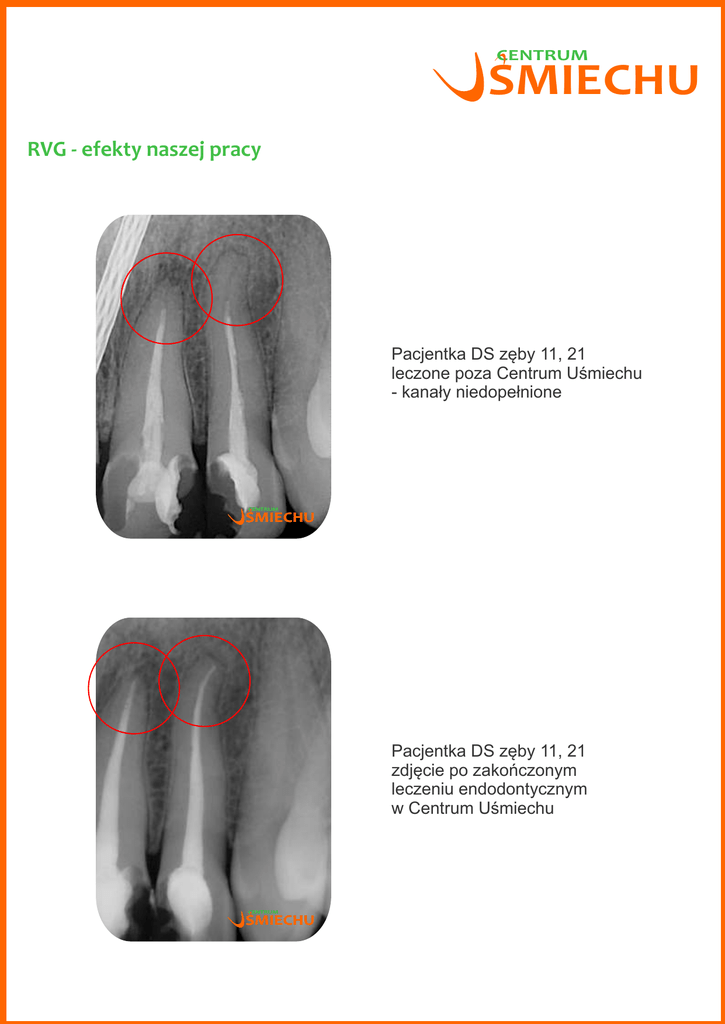

Pacjentka DS zęby 11, 21

leczone poza Centrum Uśmiechu

- kanały niedopełnione